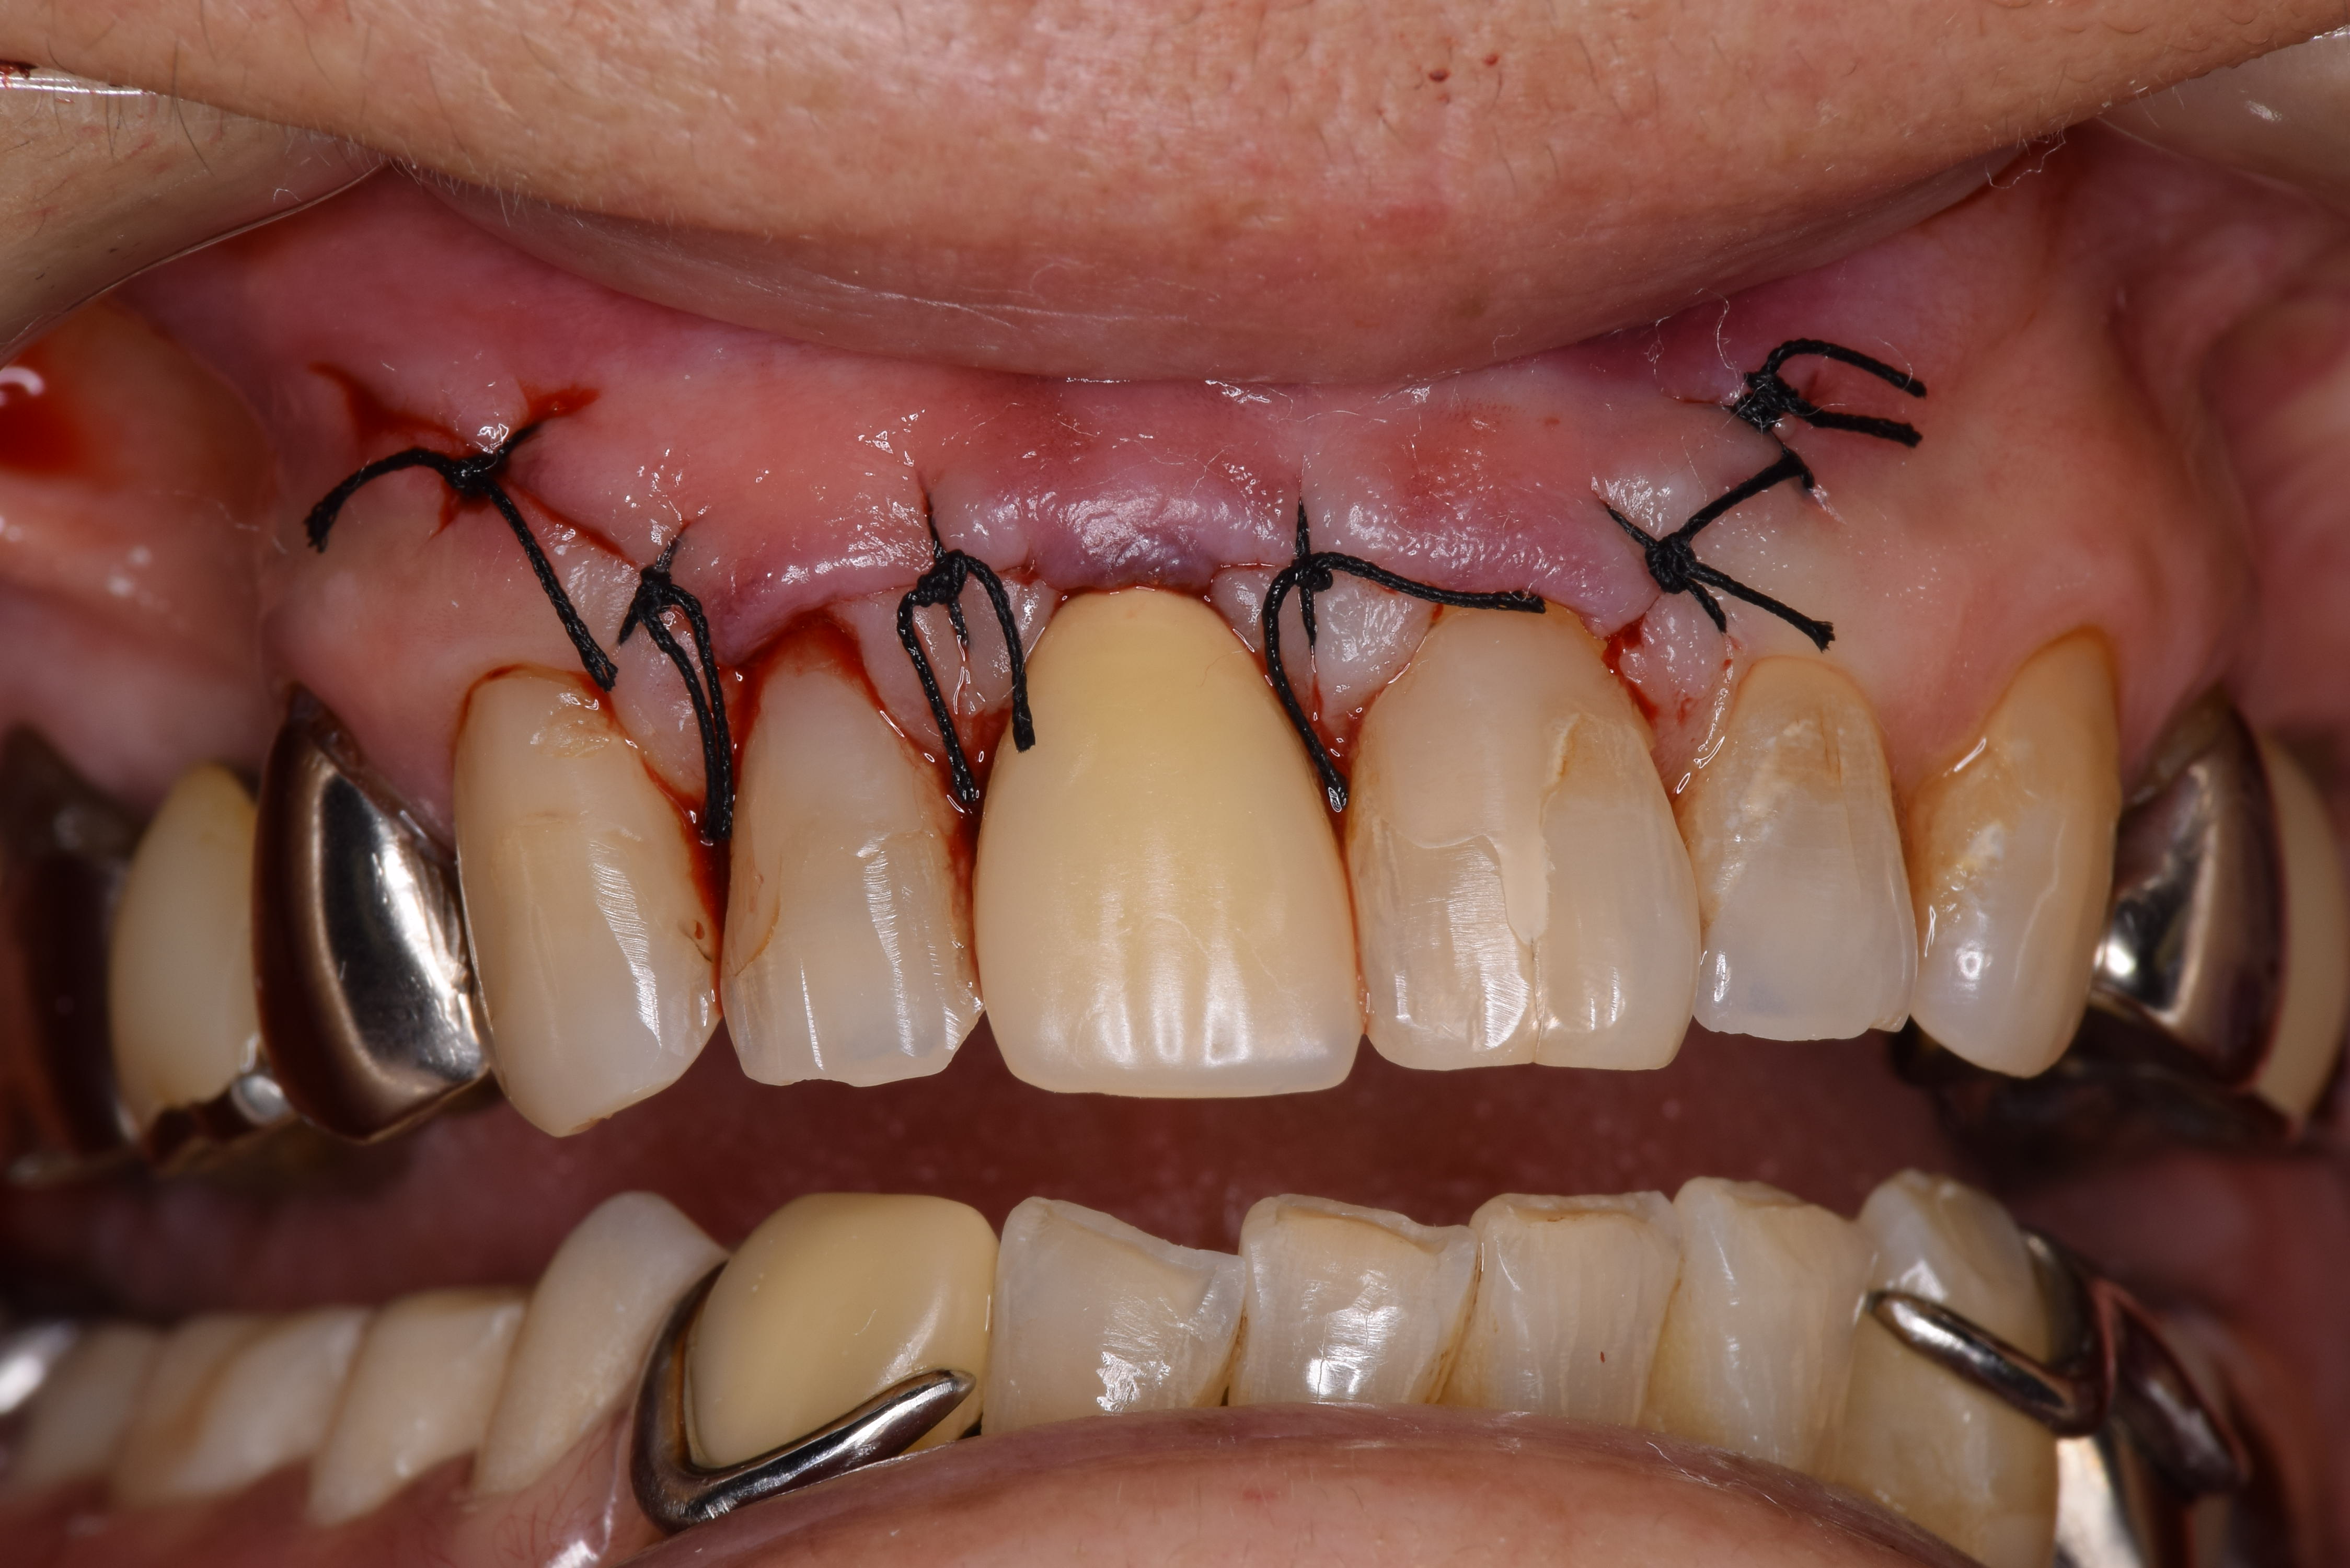

根の先を切り、人工骨を移植し、縫合しました。

抜糸時です。残念ながら症状が消えたためかその後来院が途絶えてしまい経過を追うことが出来ませんでした。